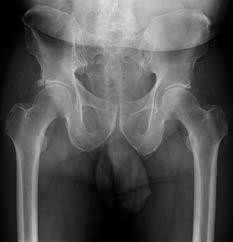

Question 8

A 13-year-old overweight boy presents with a 3-week history of right groin and knee pain. He walks with a limp. On examination, when his right hip is flexed, it obligatorily externally rotates. Radiographs show a slip of the proximal femoral epiphysis. Which radiographic line is used to diagnose this condition?

Explanation

The clinical scenario describes Slipped Capital Femoral Epiphysis (SCFE). Klein's line is drawn along the superior edge of the femoral neck on an AP pelvic radiograph. In a normal hip, this line should intersect a portion of the lateral capital femoral epiphysis. In SCFE, the line passes superior to the epiphysis or intersects less of it compared to the contralateral normal side (Trethowan's sign).